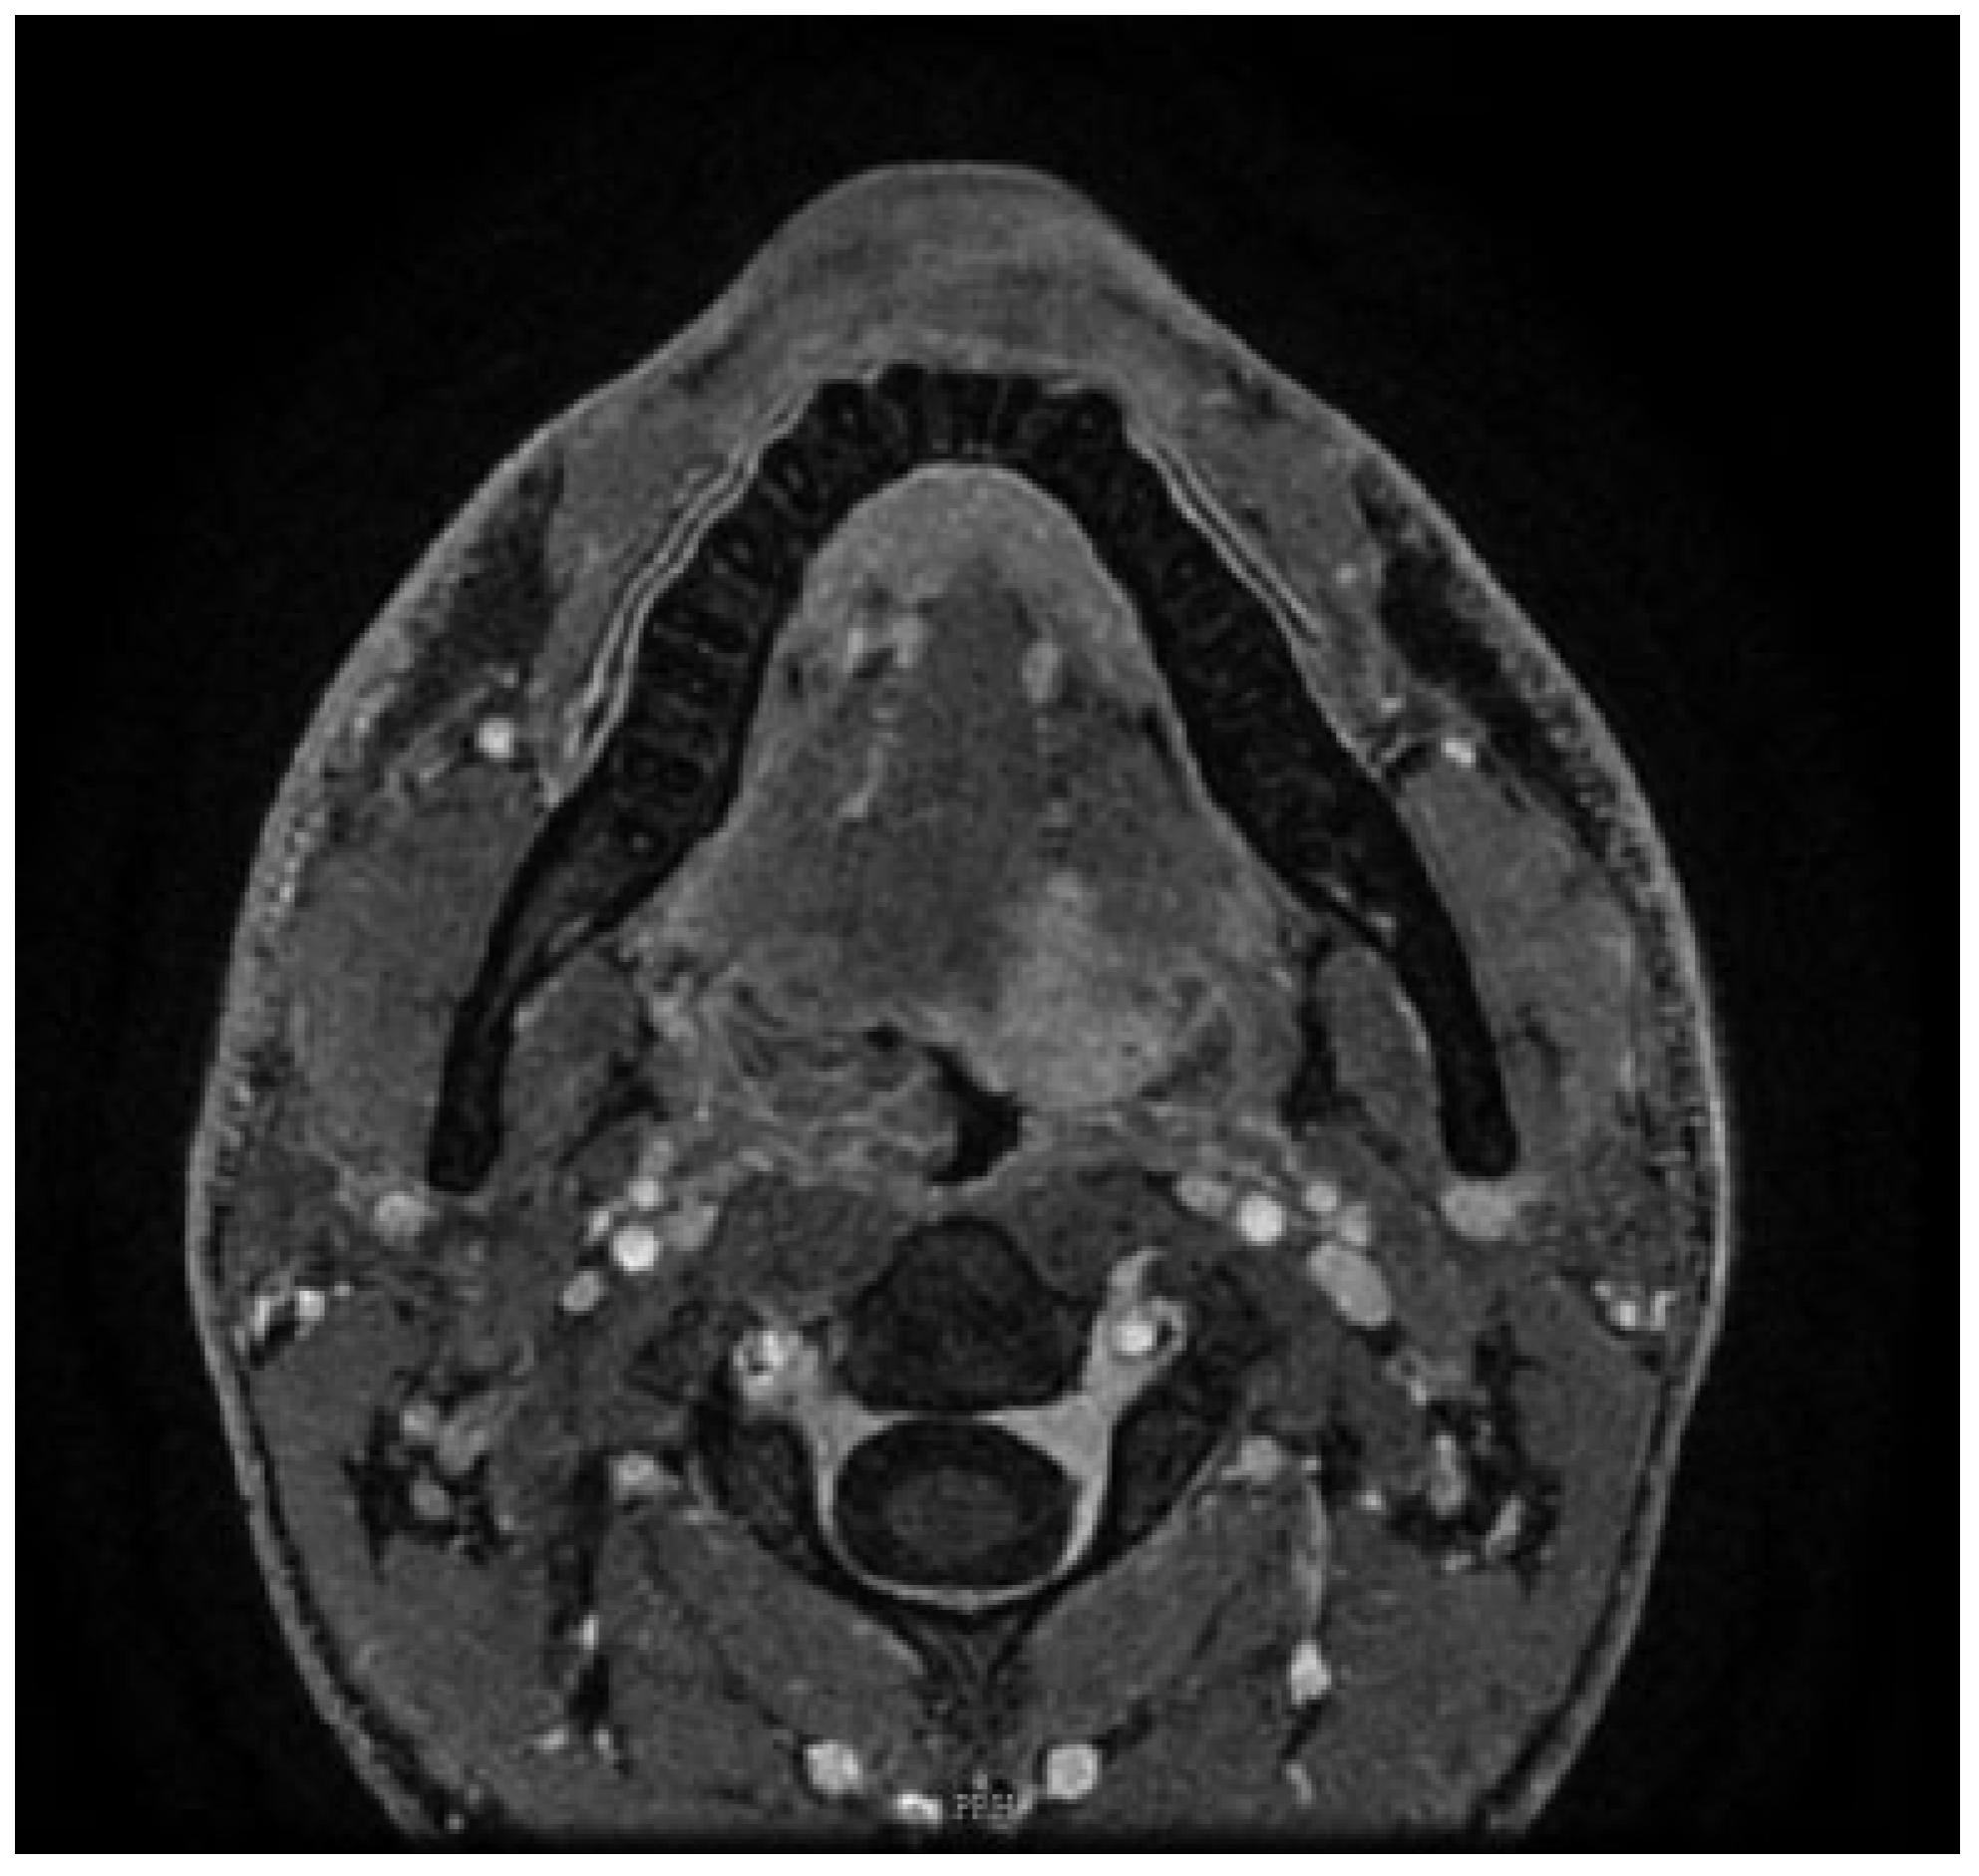

On clinical examination, the patient was fully dentate with an interincisor diameter of greater than 3.5 cm. On endoscopic examination, there was an exophytic growth arising from the left base of the tongue of size 3.5 × 2 cm, with a lateral extension to the left tonsillolingual sulcus. It extended medially toward the right base of tongue, not crossing midline in the oral tongue anteriorly and stopping short of vallecula posteriorly. The rest of pharynx and larynx appeared normal in structure and function. There were no palpable lymph nodes in the neck. Hence, it was staged as cT2N0M0 as per AJCC (American Joint Committee on Cancer; 7th Edition). A contrast-enhanced magnetic resonance imaging (MRI) of the head and neck was performed, which revealed a 1.8 × 1.6 × 3.3 cm enhancing lesion involving the base of the tongue to the left of midline indenting on the left tonsil (Figure 1). The lesion was seen extending till the midline of the tongue, involving the genioglossus and intrinsic muscles of the tongue. There was no significant cervical lymphadenopathy. There were no focal lung lesions on computed tomography (CT) of the chest. The patient’s case was discussed in the Head & Neck Multidisciplinary tumor board, and the patient was counseled for robotassisted surgery of left base of tongue with left level (I–III) neck dissection including selective arterial ligation, tracheostomy, and left radial forearm fasciocutaneous free flap.

Figure 1. Axial view MRI with contrast enhancement, showing the tumor of left side involving the base of the tongue.